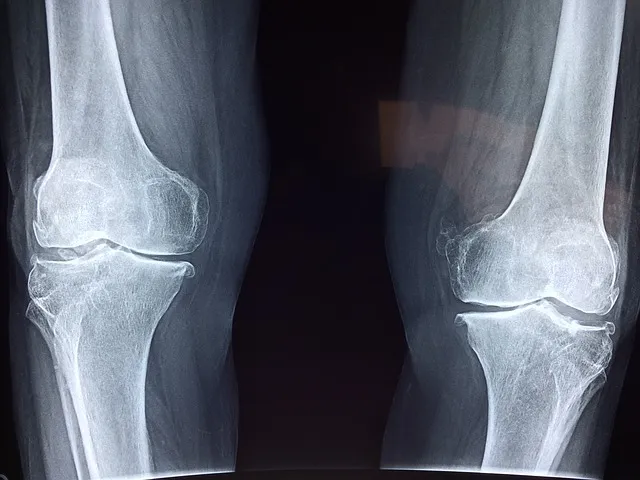

퇴행성 관절질환은 다양한 특징과 증상을 가지고 있습니다. 가장 흔한 퇴행성 관절질환은 골관절염으로, 주로 무릎, 엉덩이, 손목, 척추 등의 관절에 발생합니다. 이 질환은 통증, 관절 감각 이상, 관절 운동 제한, 관절 부종, 관절 가동성 감소 등의 증상을 유발합니다. 퇴행성 관절질환은 관절의 형태 변화, 연골 파괴, 골절 등을 동반할 수 있습니다.